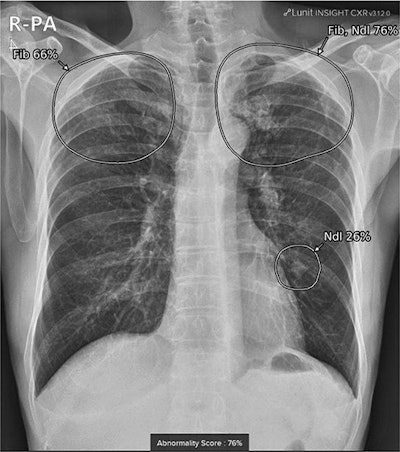

When patients undergo a chest x-ray, the software automatically analyzes the image and attaches a secondary file to the original image in the hospital’s PACS. Clinicians then may refer to the AI results, which are displayed with a contour map, abbreviations, and an abnormality score.

A true positive case in a 72-year-old male with a granuloma on chest x-ray after visiting the neurology outpatient clinic for memory disturbance. A small lung nodule was detected in the left-middle to lower lung field by AI software, with an abnormality score of 26%. Co-existing fibrosis was suspected in the apex of bilateral upper lungs, with an abnormality score of 76%. Image courtesy of Scientific Reports.